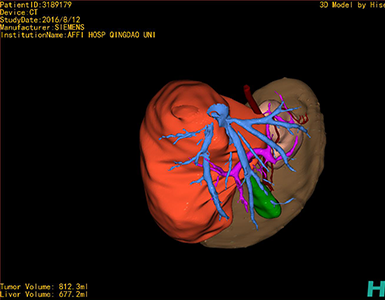

将0.625mm双源薄层CT资料的静脉期和动脉期Dicom格式文件导入海信CAS系统。

通过调节窗宽窗位调整CT序号,对肿瘤,肝实质,胆囊,下腔静脉,肿瘤,肝动脉、门静脉及肝静脉等进行三维重建;系统自动计算肿瘤体积和肝脏体积。

模拟手术操作,自动计算切除肿瘤体积。肝脏体积为660.9ml,肿瘤体积为812.3ml,肿瘤体积为肝脏体积的122.9%,通过比对3-4岁正常肝脏体积为522.63±121.24 ml,肿瘤所占比例较大,且包裹右侧肾脏、及腹腔大血管,手术无法完整切除肿物,不建议给予手术治疗。